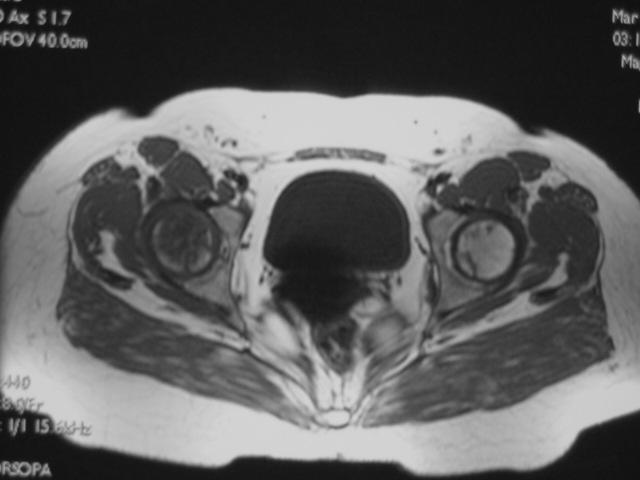

MRI扫描技术

患者取仰卧位,扫描范围自髋臼上3cm至股骨粗隆下。

层厚5mm,层间距1mm连续扫描。

选择自旋回波SE序列T1WI、T2WI及STIR冠状面扫描,横轴位T1W扫描。